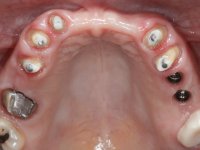

Female patient, 43 years old non-smoker. After a clinical and imaging examination, the patient presented teeth 1.7 / 1.4 / 1.3 / 2.2 / 2.3 / 2.4 / 2.6 with endodontic treatment in the upper jaw, showing absence of teeth 1.6 / 1.5 / 1.2 / 1.1 /2.1 and 2.5, and was rehabilitated with a 10-element monobloc metal-ceramic bridge. The anterior maxilla presented extensive vertical and vestibular bone reabsorption. In the lower jaw, two implants were placed at the site of teeth 4.6 and 4.5 rehabilitated with a metal-ceramic bridge. Teeth 3.6 and 3.7, with endodontic treatment, were rehabilitated with intra-radicular posts and a two-element metal-ceramic bridge. The antero-inferior teeth presented class III and IV resin restorations. Tooth 3.5 was absent. The patient had a vertical dimension of occlusion reduction, accompanied by accentuated dental wear and some ceramic fractures. Good oral hygiene.

Alginate impressions were made at both arches arcades, accompanied by intermaxillary registration relations and collecting information with facial bow facial bow. In the laboratory, a provisional bridge with 13 elements in autopolymerizable acrylic was built, in which a metallic reinforcement was included. Teeth 1.7 / 1.4 / 1.3 / 2.2 / 2.3 / 2.4 and 2.6 were used as pillars. The metal-ceramic bridge was removed after performing longitudinal cuts with diamond burs. The dental abutments were reprepared and the temporary bridge was relined in the mouth with self-curing acrylic. After confection of the provisional bridge, a gingival epithesis was made using composite resin with gingival tonality in order to function as a mock-up, which allowed the patient to preview the possibility of using gingiva shade ceramics in the final work. This option was approved by the patient. Subsequently, the placement of two implants in the first quadrant was planned and executed. The provisional monoblock was removed for placement of the implants, and after surgery was again cemented provisionally. After the osseointegration period, the impressions were made to the maxilla. In the anterior zone, impregnated gingival retraction cords were used, and in the posterior areas, kaolin paste was used. Implant printing utilized the open tray technique. The printing material used was soft and regular putty addition silicone, both fast-setting. In the laboratory, the model of provisional restorations and the gingiva epithesis mock-up served as orientation for waxing the infrastructure. The plaster work model and the waxing of the infrastructure were placed in a laboratory scanner and yielded a digital work model, in which the scanning of the waxed infrastructure was superimposed. This overlay facilitated the CAD design of the Zr infrastructure. Subsequently, the CAD drawing for a CAM milling process provided the Zr pieces. The infrastructure was pigmented with a pinkish coloration, which favors the subsequent placement of gum shade ceramic. During the modeling of the infrastructure, the need to increase the occlusal wear on tooth 1.4 was detected. This was done in the real working model cast and an acrylic wear control guide was created, which accompanied the proof of the infrastructures. Corrective wear and Zr parts test were performed in mouth. During the test, the color choice of the gum shade ceramic was reassessed. The treatment was finished in the laboratory, and after approval by the patient, was definitively placed in the mouth.